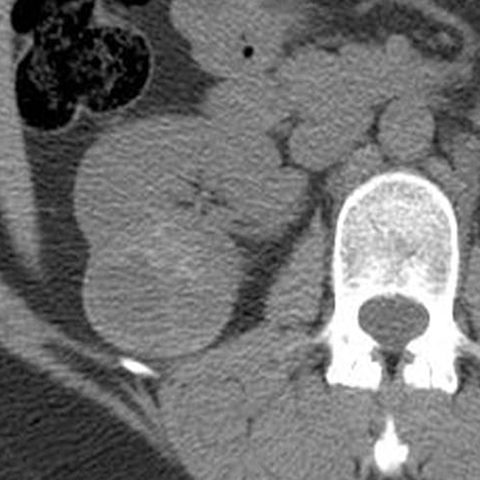

67-year-old male with flank mass and hematuria [1 of 3]